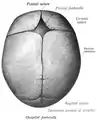

La suture sagittale (ou suture bipariétale ou suture interpariétale ou suture pariétale ou suture rhabdoïde) est la suture crânienne qui relie les bords supérieur des deux os pariétaux.

Elle présente deux repères anatomiques : le bregma formé par son intersection avec la suture coronale, et le vertex du crâne.

Suture sagittale d'un nouveau-né, vue de dessus.